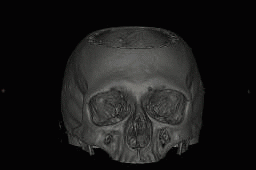

VHSは、CT検査の寝台(テーブル)がノンストップで連続往復しながら撮影し、経時的なデータを収集していく新しいテクノロジーです。

Volume Helical Shuttle(以下VHS)によるCT撮影は、テーブルスピードが安定するまで の加速時ならびにテーブルが停止するまでの 減速時のデータも画像化できるため、無駄な被ばくを軽減するだけでなく、4D画像の時間 分解能が向上し、30cm以上の広範囲における4D画像も容易に得ることが可能です。